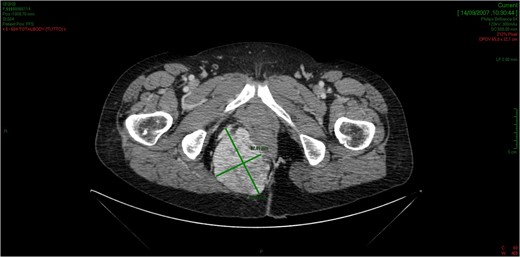

CT showed an hyperintense and inhomogeneous solid lesion taking up the right ischiorectal fossa (maximum diameter of about 10 cm), extended cranially until impressing the wall of the rectal ampulla, with no apparent infiltration (Figs 2 and 3). The lesion presented an intense contrast enhancement, sign of a rich vascularization (Fig. 4).

The CT scan demonstrates a solid neoformation in the right ischiorectal fossa.

The lesion extends cranially until impressing the wall of the rectal ampulla, with no apparent infiltration.